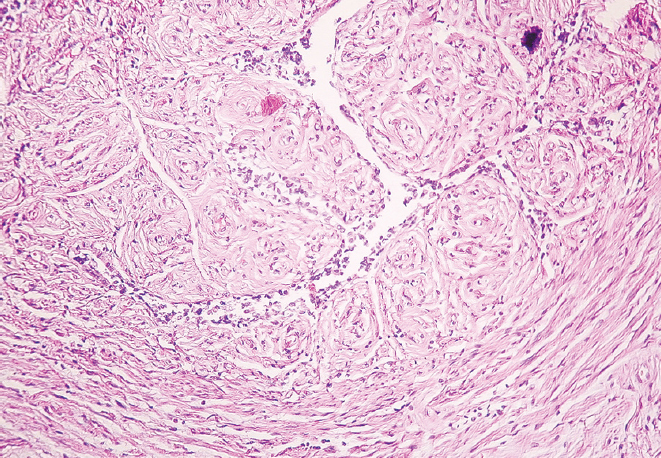

Материалы и методы. Исследование выполнено на секционном материале 70 рожавших женщин, которых разделили на две группы: в первую группу включили 34 женщины молодого возраста (22–35 лет), во вторую группу — 36 женщин старческого возраста (75–88 лет). Определяли наружный диаметр перешейка и воронки маточных труб. Для гистологического исследования изъятые при аутопсии фрагменты маточных труб в местах перешейка и воронки окрашивали пикрофуксином по Ван Гизону и гематоксилином и эозином.

Результаты. Установлено уменьшение показателей наружного диаметра перешейка и воронки обеих маточных труб женщин от молодого возраста к старческому (p < 0,01). В старческом возрасте определено преобладание параметров наружного диаметра перешейка и воронки правой маточной трубы в сравнении с показателями левой маточной трубы (p < 0,01), наряду с этим в молодом возрасте выявлена лишь тенденция к превалированию значений диаметра перешейка и воронки правой маточной трубы (p > 0,05). Гистологическое исследование показало наличие утолщенных складок слизистой оболочки и уплощенного эпителия в исследуемых областях у женщин старческого возраста, истончение слоев мышечной оболочки и разрастание соединительной ткани в сравнении с образцами, взятыми для исследования у женщин молодого возраста.

Заключение. Морфологическая перестройка перешейка и воронки маточных труб от молодого к старческому возрасту заключается в утолщении складок слизистой оболочки, уплощении эпителия, разрастании соединительной ткани в стенке и уменьшении их наружного диаметра с преобладанием параметров в правой маточной трубе.